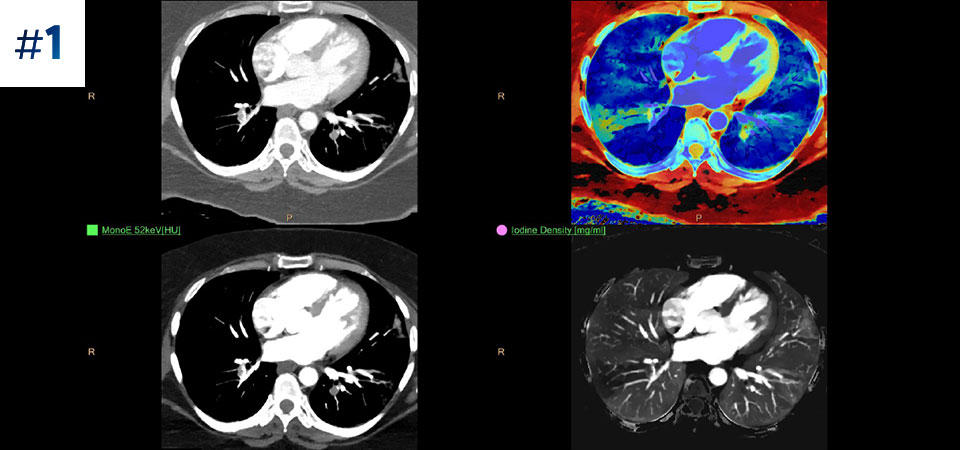

Prin tomografia computerizată bazată pe detector spectral, puteți achiziționa date la mai multe nivele de energie - convenționale și spectrale – printr-o singură expunere și fără protocoale speciale de scanare, pentru o mai bună caracterizare și vizualizare a țesuturilor.

Scanează ca de obicei O singură scanare pentru date convenţionale şi spectrale obţinute rapid, cu doză redusă, pentru fiecare pacient, de fiecare dată.

Are întotdeauna disponibilă componenta spectrală Rezultate 100% spectrale, pentru toate scanările care sunt întotdeauna disponibile la cerere, chiar și retrospectiv.

Reduce numărul de examinări ulterioare O mai bună caracterizare și vizualizare a țesuturilor poate reduce nevoia de scanare ulterioară pentru examene suboptime și descoperiri accidentale.